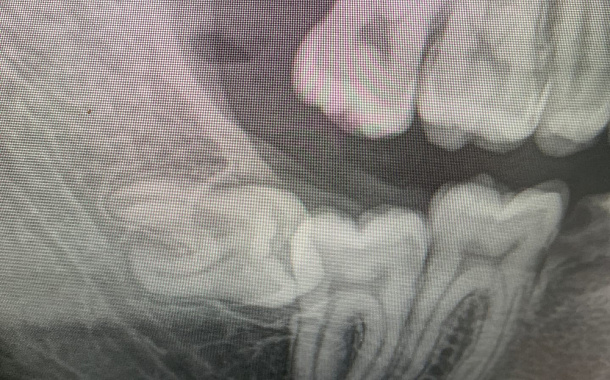

Удаление «зуба мудрости» - не простая манипуляция из-за множества факторов, усложняющих процедуру:

1. Затрудненное прорезывание – хроническое воспаление мягких тканей вокруг зуба и частые эпизоды его обострения.

2. Неправильное положение зуба в челюсти, часто зубы «мудрости» прорезаются частично или не прорезаются в полость рта вообще, имея при этом горизонтальный наклон и близкое, а иногда переплетающееся расположение относительно важных анатомических образований (нижнечелюстной нерв, корни соседних зубов.

3. Аномальная форма коронки зуба, в среднем коронка нижнего зуба «мудрости» больше по размерам относительно других жевательных зубов.

4. Сложная анатомия корней зубов «мудрости» - тонкие и скривленные корни, часто плотно сросшиеся между собой «в замок» и с костной тканью.

5. Близость и взаимосвязанность важных анатомических образований челюстно-лицевой области - нижнечелюстной нерв, гайморова пазуха, небная артерия, мышцы.

Сложное анатомическое расположение и анатомия самих зубов, близкое расположение важных анатомических образований (нижнечелюстной канал, гайморова пазуха) и их взаимосвязанное расположение с корнями «восьмых» зубов, требует от врача-хирурга тщательного анализа клинической ситуации, данных 3D рентгенографии и оценки всех возможных рисков и осложнений, как во время операции, так и после ее проведения.

Удаление наклоненной восьмерки

Пациента отправили на удаление восьмёрки из-за невозможности пролечить кариес между восьмым и седьмым зубом.

Восьмерка имеет наклон в горизонтальном направлении и упирается в седьмой зуб. Сложность в том, что зуб находится на нерве, и ошибки при удалении таких зубов могут привести в последствии к онемению губы и подбородка со стороны удаляемого зуба.